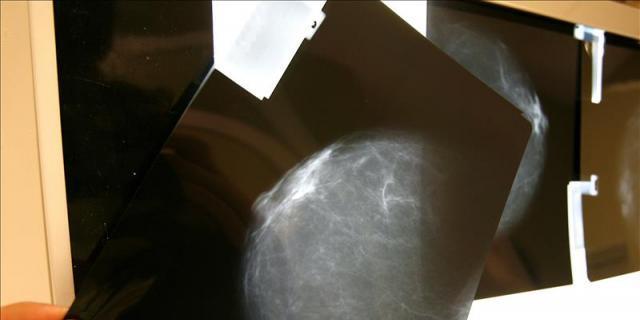

El Servicio de Salud Madrileño (Sermas) ha sido condenado a indemnizar con 60.000 euros a una mujer a quien le fue diagnosticado con retraso un cáncer de mama en el Centro de Salud Prosperidad, de la capital.

Según la sentencia del Tribunal Superior de Justicia (TSJ) de Madrid, tramitada por El Defensor del Paciente, la denunciante, M. P. A., recibió un primer ciclo de quimioterapia el 10 de noviembre de 2009, más de siete meses después de la primera ecografía mamaria cuyo resultado, erróneamente, fue considerado como benigno.

Esta prueba, realizada el día 15 del mismo mes detectó la presencia de un "nódulo benigno en mama izquierda".

Posteriormente, el 7 de septiembre, cuando ya habían sido realizadas una mamografía y una ecografía, una biopsia resultó "compatible con carcinoma de mama con sospechosas de adenopatías metastásicas y mestástasis hepáticas."

El Servicio de Oncología desestimó la intervención quirúrgica y optó por un tratamiento paliativo de quimioterapia cuyo primer ciclo de quimioterapia se le administró el 10 de noviembre, "siete meses después de la primera ecografía mamaria cuyo resultado, erróneamente, se consideró como benigno".